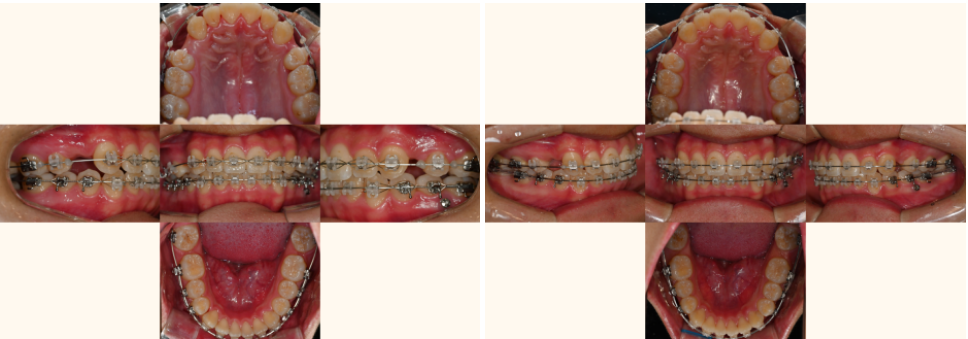

| 3. 종결 단계

25.06.12

매복되었던 치아는

완전히 정상 위치로 나와서

제 기능을 다하게 되었고,

사랑니도 성공적으로

어금니 자리에 정착하여

저작 기능을 담당하게 되었습니다.

특히 주변 치조골도 자연스럽게 재생되어

마치 원래부터 그 자리에 있었던 것처럼

건강한 상태를 보인다는 거예요.

절단연 교합은 완전히 개선되어

윗니가 아랫니를 적절히 덮는

정상적인 교합 관계가 확립되었고,

정중선도 완벽하게 일치하여

기능적으로나 심미적으로나

만족스러운 결과를 얻었습니다.